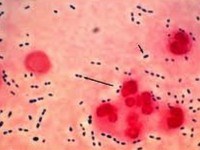

Znate li simptome streptokokne infekcije?

objavljeno prije 2 godine i 2 mjesecaStreptokok je uzročnik brojnih oboljenja, no najčešće bolesti koje uzrokuje je upala grla (angina) i šarlah. No, osim toga se može dogoditi da smo si sami krivi - nismo… više »